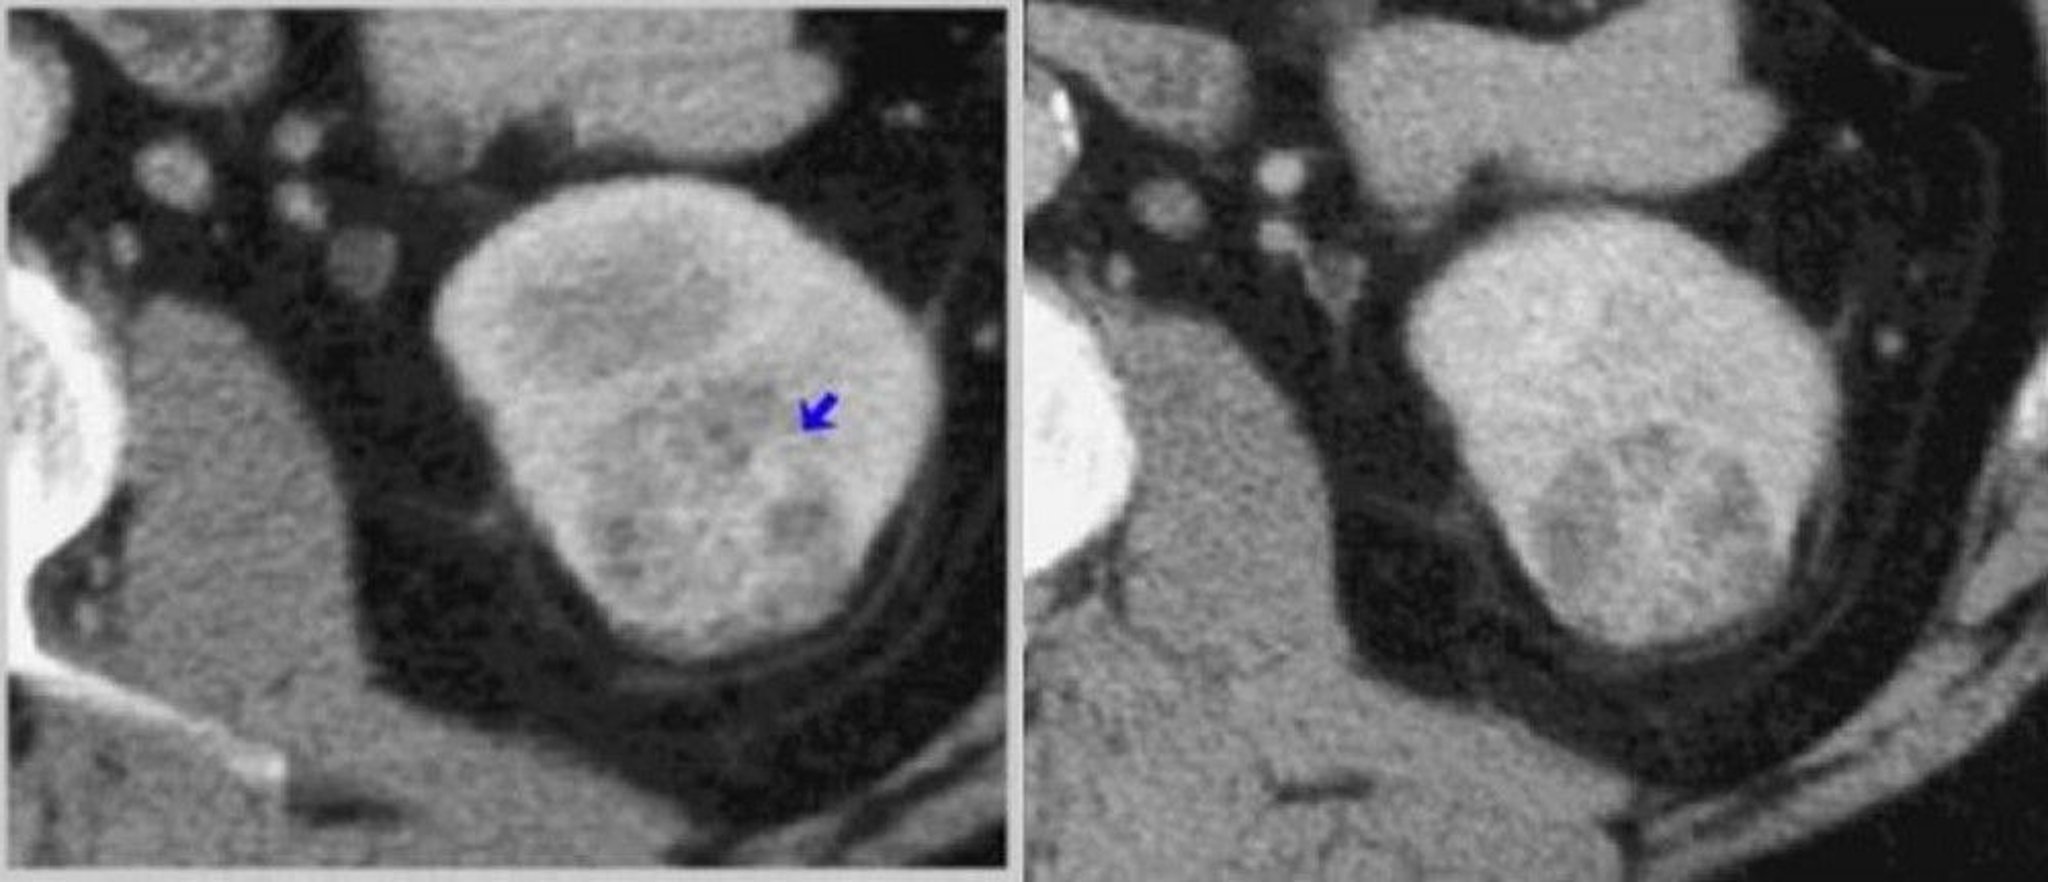

CT-Kontrastmitteluntersuchung der Niere (kortikomedulläre und nephrogene Phasen)

Links zeigt ein CT-Scan der kortikomedullären Phase einen heterogen verstärkten Tumor (Pfeil). Rechts ist der Tumor in einem nephrographischen Phasen-CT-Scan besser zu erkennen.